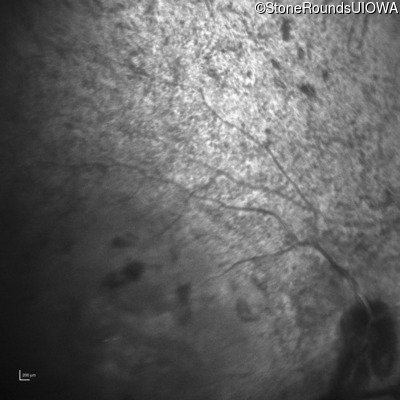

Infrared Fundus Photograph - Right - Light Perception

Exemplar